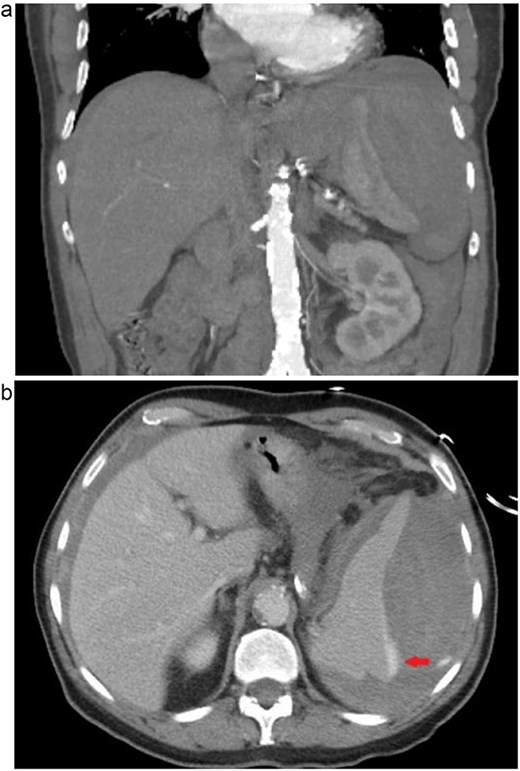

A 69-year-old male patient with a history of 50 pack years of smoking, atrial fibrillation on apixaban, coronary artery disease, and hypertension presented to the emergency department at a tertiary care hospital by ambulance with acute onset abdominal pain and a syncopal event at home six hours prior. The patient was hypotensive with blood pressure of 67/53 mmHg en route, which improved to 142/70 mmHg after 500 ml of normal saline and 5 mcg of epinephrine. An additional 1 l of saline and 1 unit of packed red blood cells were given with continued hemodynamic response. The patient reported no recent history of trauma or change in health. Bedside ultrasound revealed large volume free fluid in the abdomen. Computed tomography angiography of the abdomen demonstrated acute splenic rupture with active extravasation (Fig. 1). Tranexamic acid was administered. Prothrombin concentrate was given to reverse the apixaban. The patient again became hypotensive to 84/55 mmHg and was taken emergently for exploratory laparotomy and splenectomy. Intraoperatively, it was found that most of the splenic attachments had already avulsed. Remaining attachments to the diaphragm were taken down, the short gastric ligated, and the hilum transected. Intraoperative blood loss was 4 l, with 1.7 l returned through auto-transfusion. Postoperatively, he was admitted to the intensive care unit for monitoring overnight. The patient did not require further transfusion. He was able to transition to the surgical floor, advance diet, and discharge to home on postoperative day 5. Prior to discharge, the patient received meningococcal, pneumococcal, and Haemophilus vaccinations. No complications were identified at the 2-week postoperative follow-up outpatient visit, and the patient was able to restart his apixaban without issue. Pathologic review of the specimen did not identify abnormality to explain the rupture.

(a) Coronal computed tomographic angiogram image of ruptured spleen with large amount of surrounding perisplenic hematoma. (b) Axial computed tomographic angiogram image of ruptured spleen, arrow indicating extravasation of contrast dye.